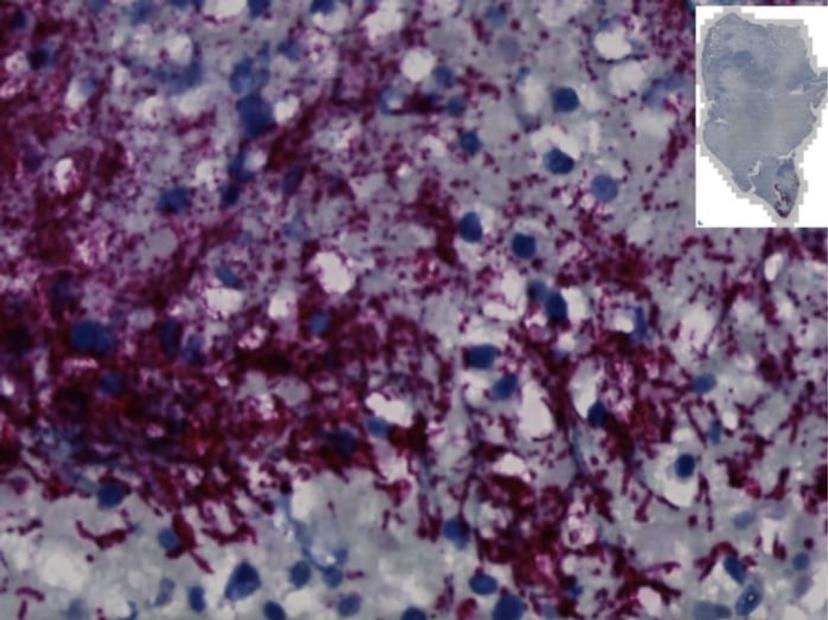

Examining colorectal cancer tumors removed from 200 patients, the Fred Hutch team measured levels of Fusobacterium nucleatum, a bacterium known to infect tumors. In about 50% of the cases, they found that only a specific subtype of the bacterium was elevated in the tumor tissue compared to healthy tissue. They also found this microbe in higher numbers within stool samples of colorectal cancer patients compared with stool samples from healthy people.

Then, comparing tumor tissue with healthy tissue from patients with colorectal cancer, the researchers found that only the subtype Fna C2 is significantly enriched in colorectal tumor tissue and is responsible for colorectal cancer growth. Further molecular analyses of two patient cohorts, including over 200 colorectal tumors, revealed the presence of this Fna C2 lineage in approximately 50% of cases.